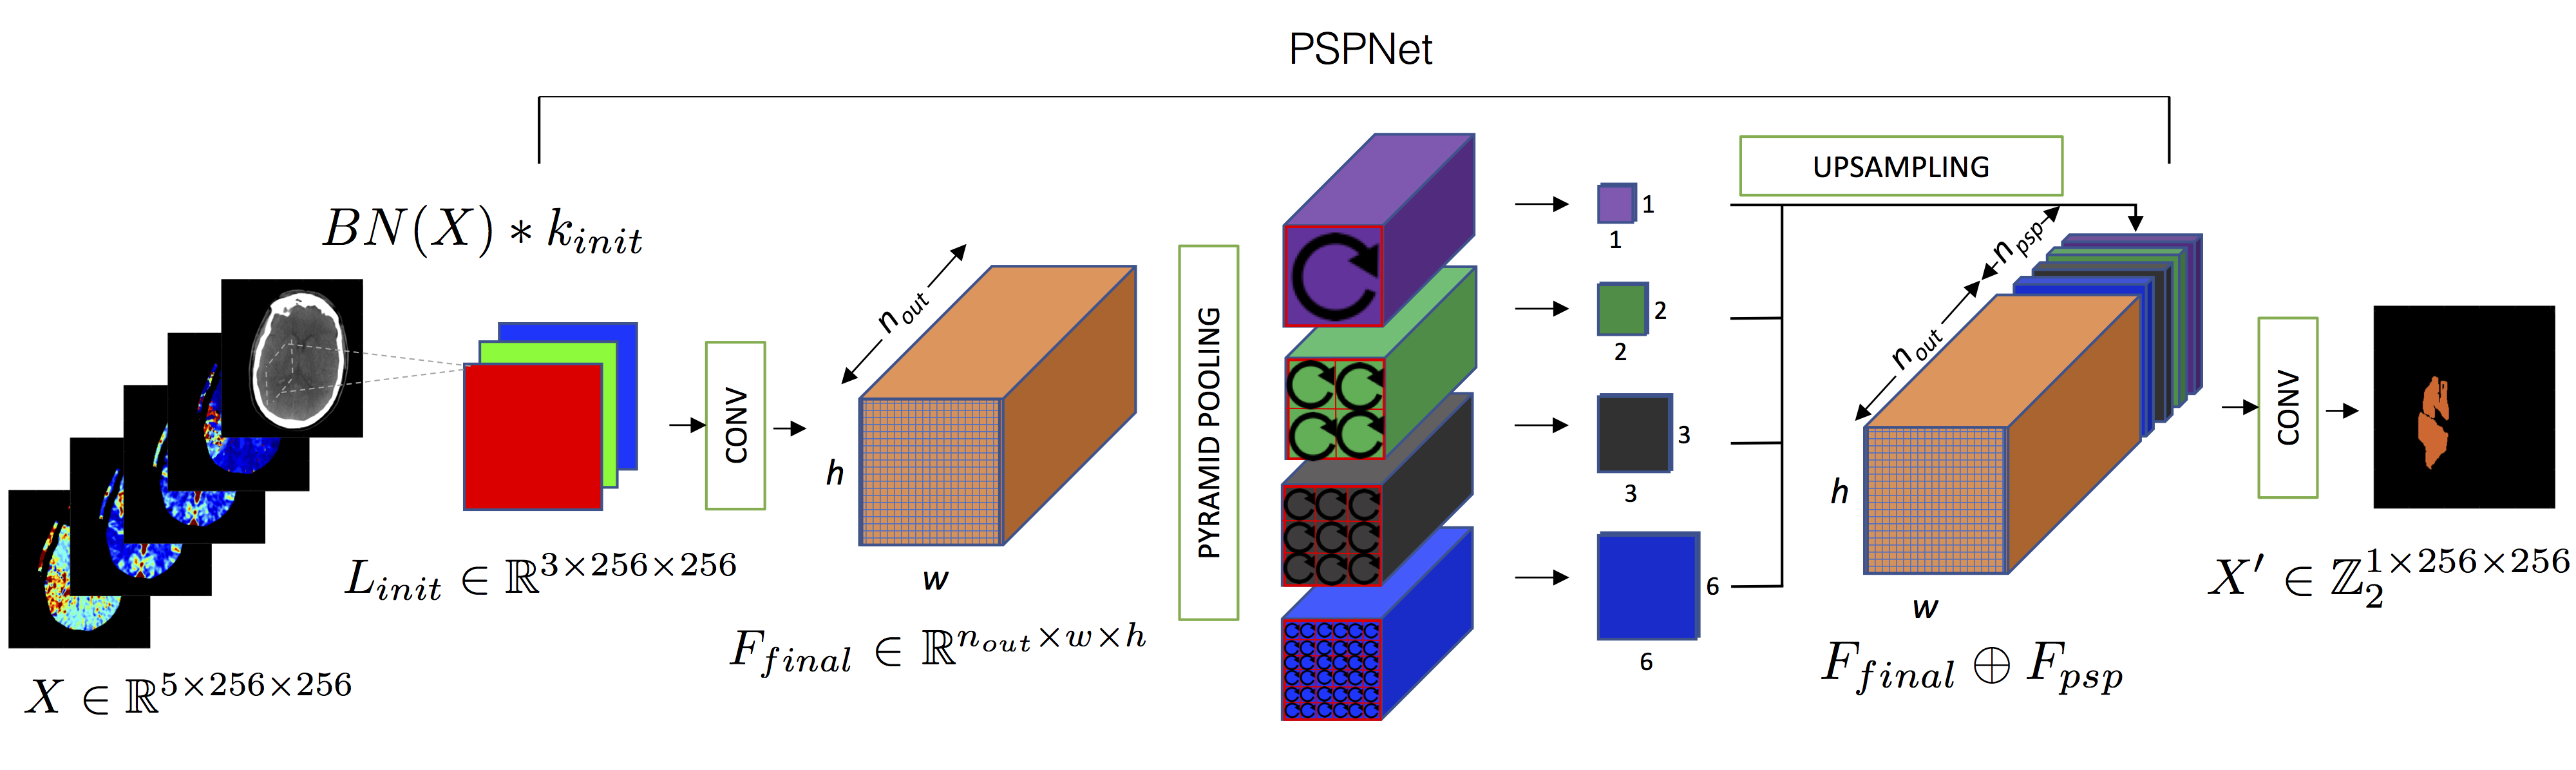

Fig. 2 illustrates the module graphically. Consider the last convolutional layer of a network, that consists of feature maps, . At the coarsest level, global average pooling (represented by circular arrows in Fig. 2) is applied to resulting in feature maps. Further average pooling operations are also applied that result in , and feature map sizes. The final features of the pyramid pooling module are derived by applying a convolution to each of the resultant feature maps (to ensure equal weighting for each pooling kernel) and upsampling (using bilinear interpolation) to match the dimensions of the final layer feature maps, . The original final layer feature maps are then concatenated to those derived from the pyramid pooling module () to give a collection of feature maps that capture both local and global context information at varying sub-regions of the input image.

We used a pre-trained PSPNet that was trained on natural images from the Pascal VOC dataset [8]. As the original network architecture accepted 3 input channels for processing RGB images, the network was modified to include an additional initializer layer that could accept multi-modal CT perfusion slices. Given a collection of stacked CT perfusion maps, the initializer layer, , first applies batch normalization [12] to standardize channel features to a common mean and variance within the batch. Following this, a 1x1 convolutional kernel, is learned to reduce the channel dimension from 5 to 3. These steps are summarized in Equation (1), where refers to batch normalization and refers to the convolution operation.

The resulting feature maps in layer , are ready to be processed using the pre-trained PSPNet weights. Correspondingly, the final layer of the network was modified to replace the 21 class prediction channels, used in Pascal VOC, with binary output channels to predict the presence or absence of ischemic stroke lesions.